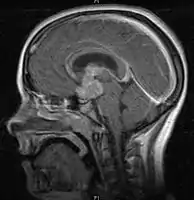

CNS Germinoma

- Mainly located in midline structures, suprasellar region or pineal gland, also basal ganglia and hypothalamus

- Pineal Gland Germinoma

- Suprasellar Germinoma